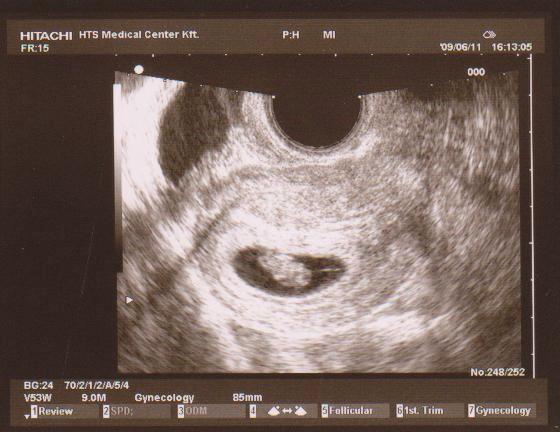

De addig is küldök egy képet Babóról:

Kép

akire79